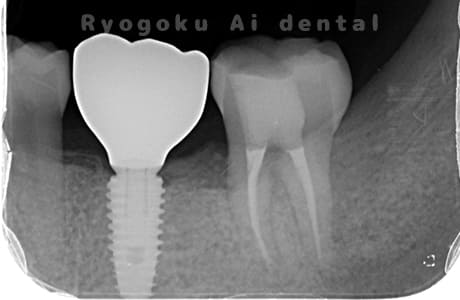

Case07

- 原因

- 右下6番歯根破折

-

- 治療内容

- インプラント治療

- 治療費用

- 約600,000円

右下の腫れが治らないとの事でご来院された患者様です。歯が割れていたため、抜歯を行い、骨に代わるお薬を入れ、インプラントを埋入致しました。経過良好で大変満足していただけました。

<リスク・副作用>

治療後、痛みや違和感、出血、腫れなどが出る事があります。喫煙者、糖尿病などの方の場合、歯が生着しない場合があります。